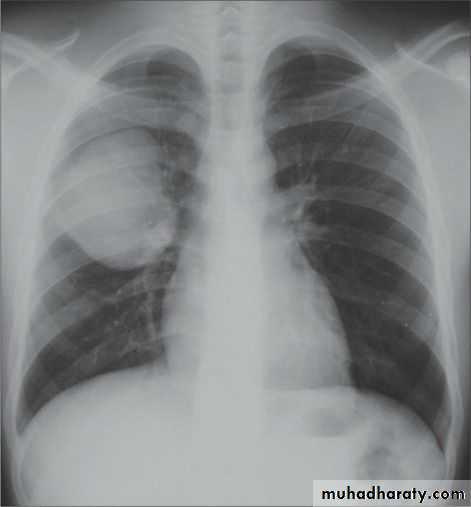

History; too shy to take of his shirt in the pool!